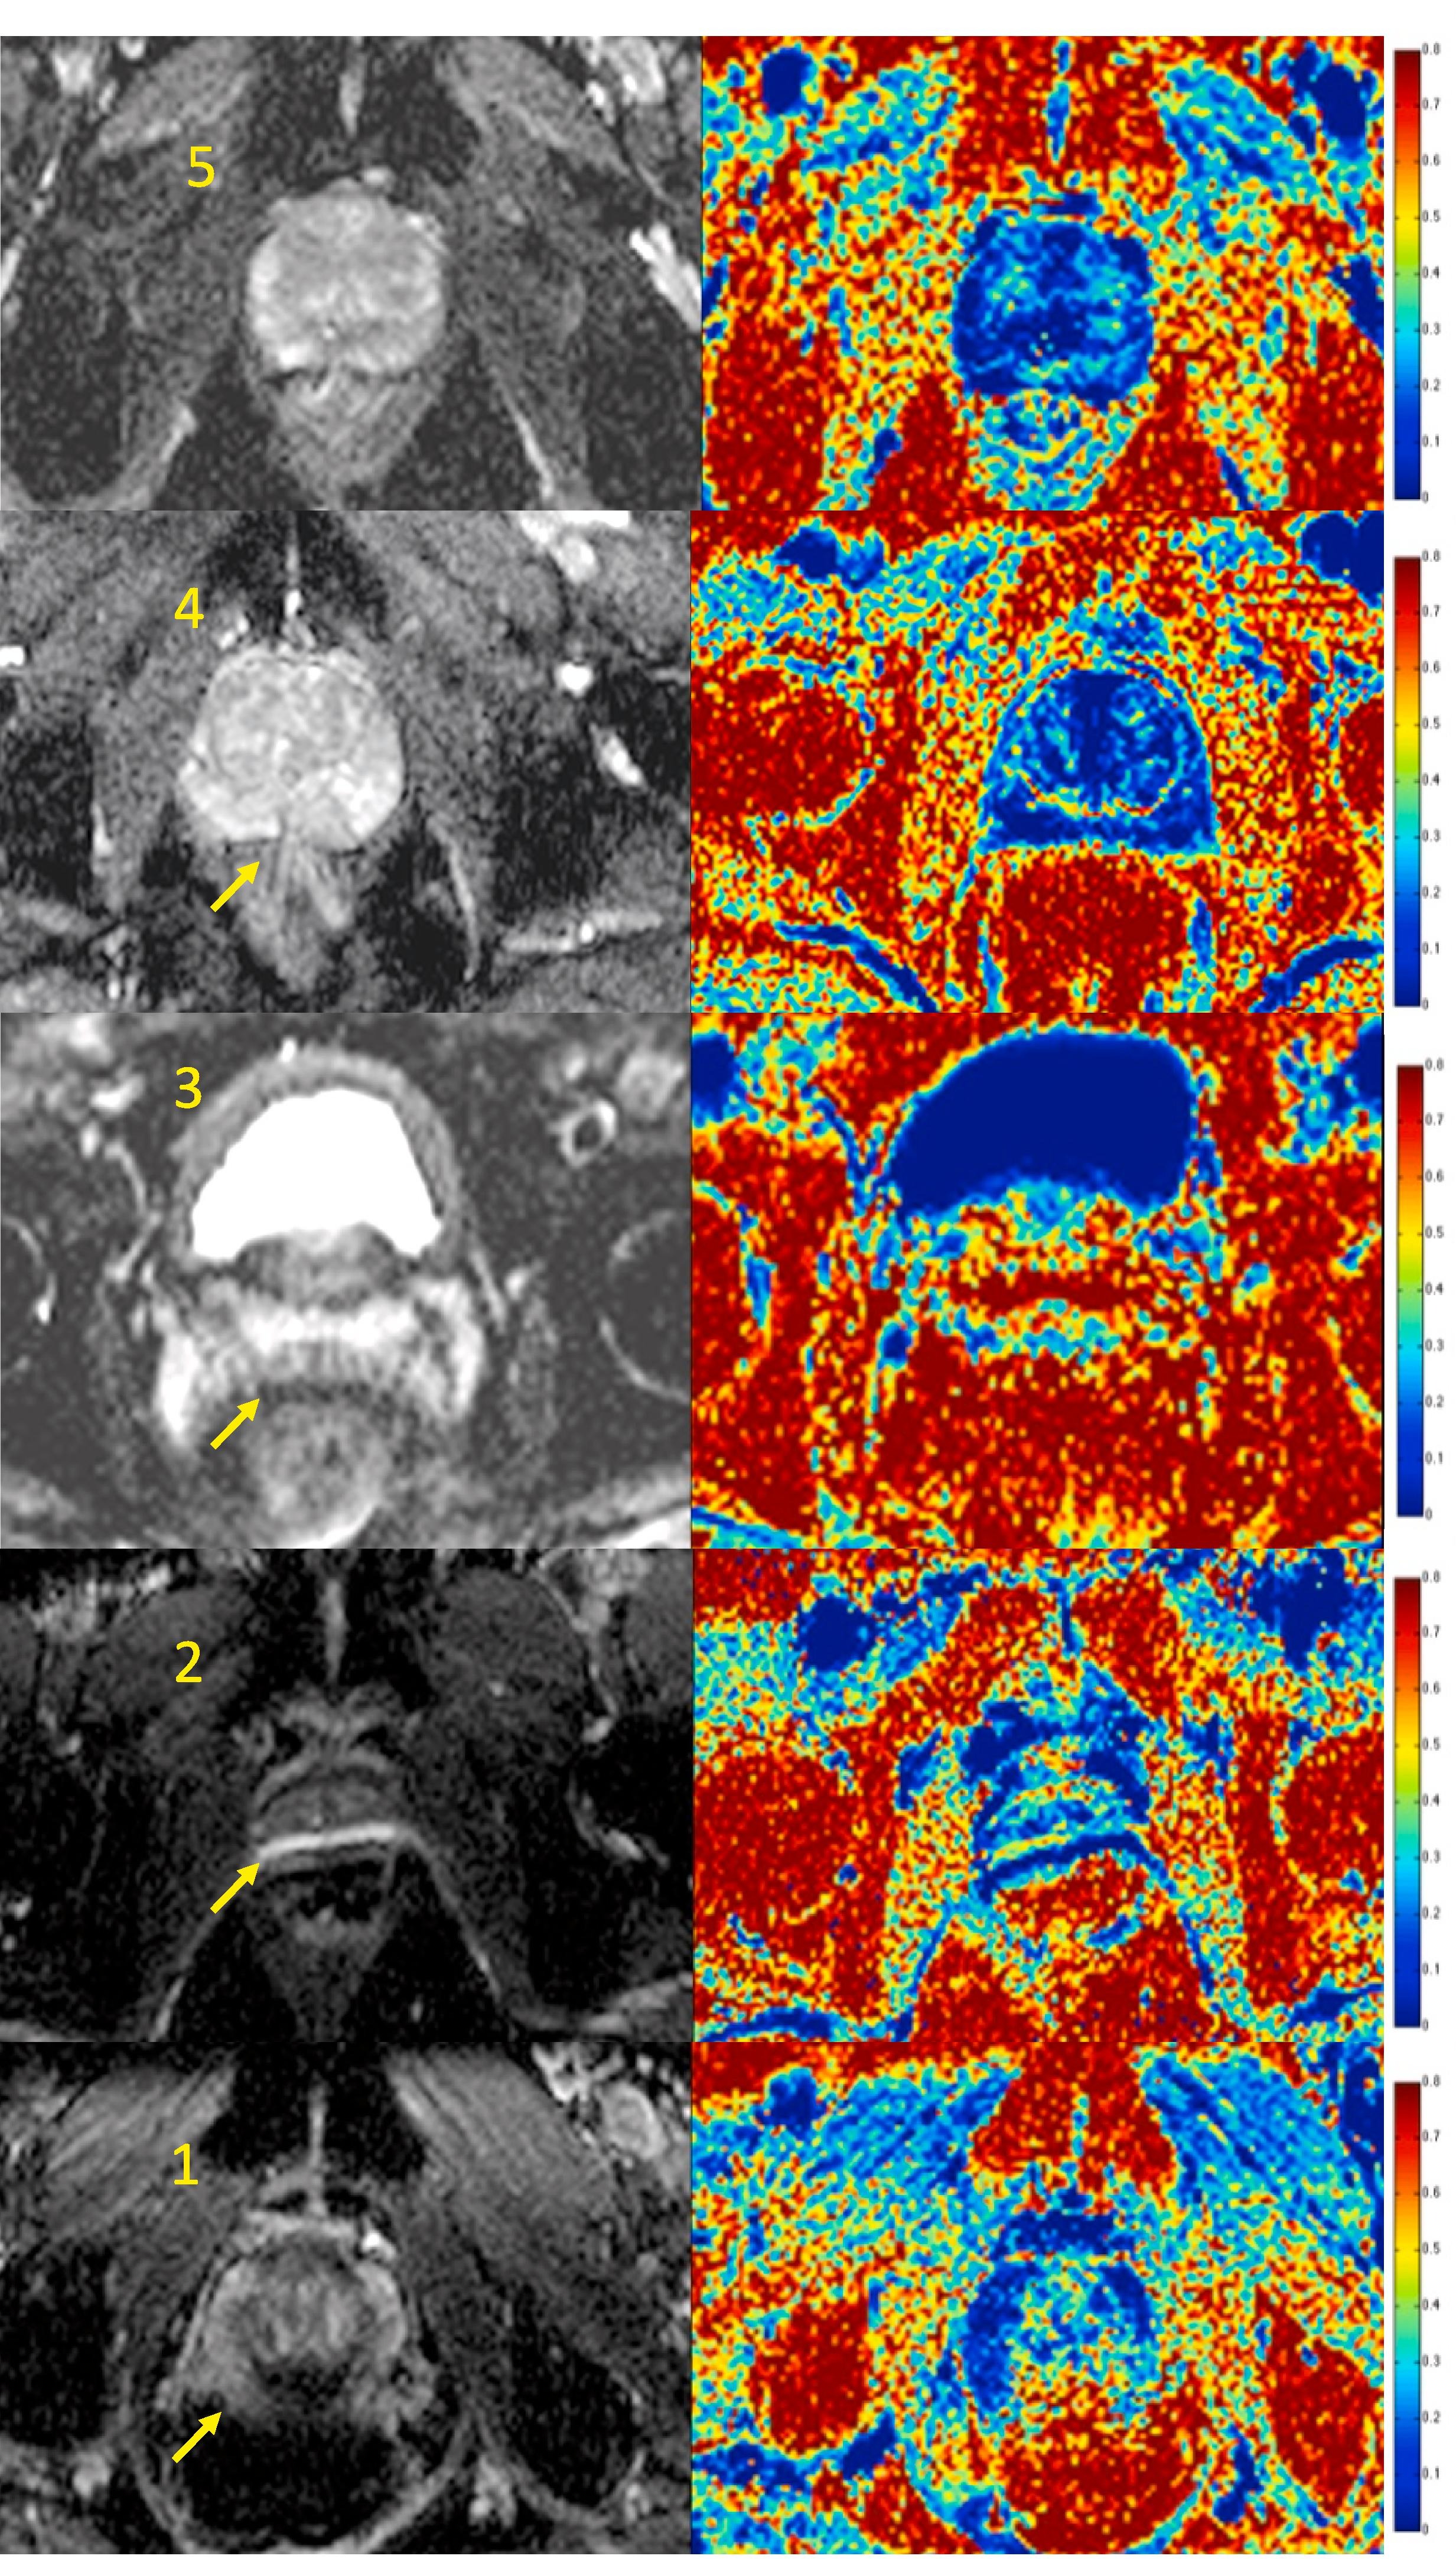

This study aimed to assess the image quality of apparent diffusion coefficient (ADC) maps derived from conventional diffusion-weighted MRI and fractional intracellular volume maps (FIC) from VERDICT MRI (Vascular, Extracellular, Restricted Diffusion for Cytometry in Tumours) in patients from the INNOVATE trial. The inter-reader agreement was also assessed.

False positives on multiparametric MRIs (mp-MRIs) result in many unnecessary invasive biopsies in men with clinically insignificant diseases. This study investigated whether quantitative diffusion MRI could differentiate between false positives, true positives and normal tissue non-invasively.